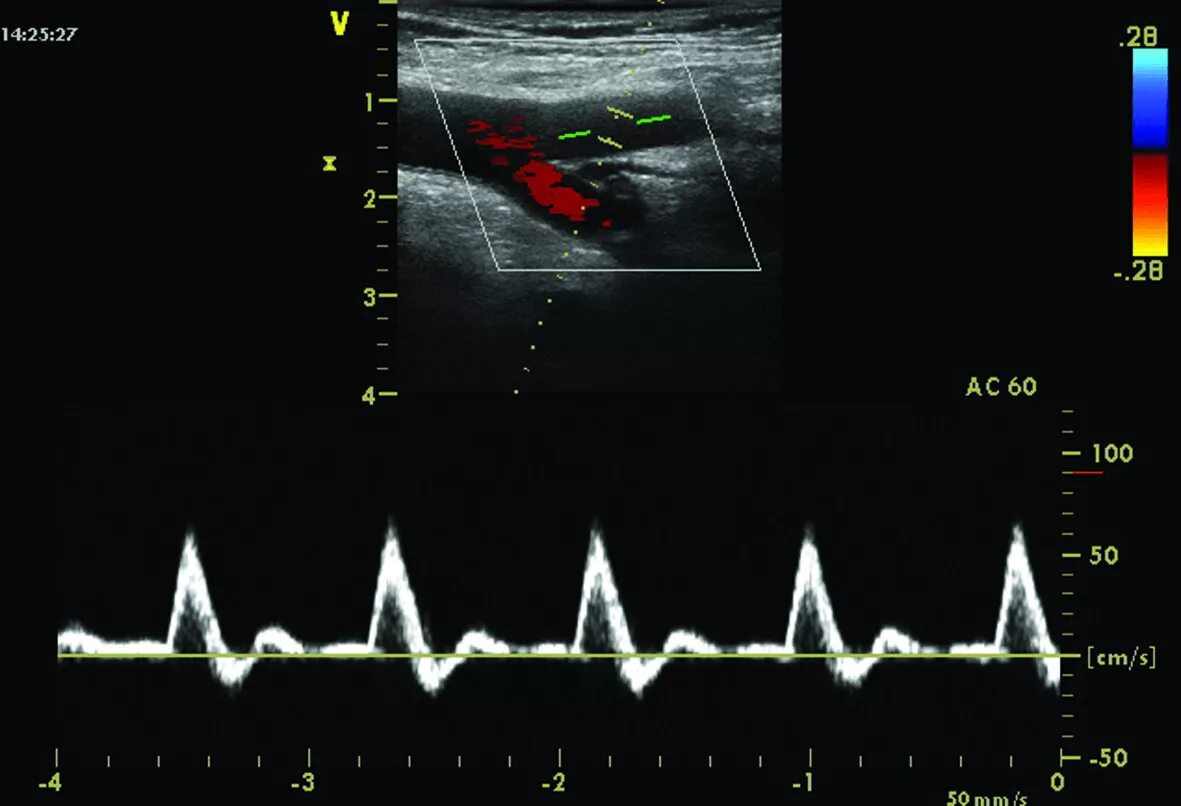

Тип кровотока 1 типа